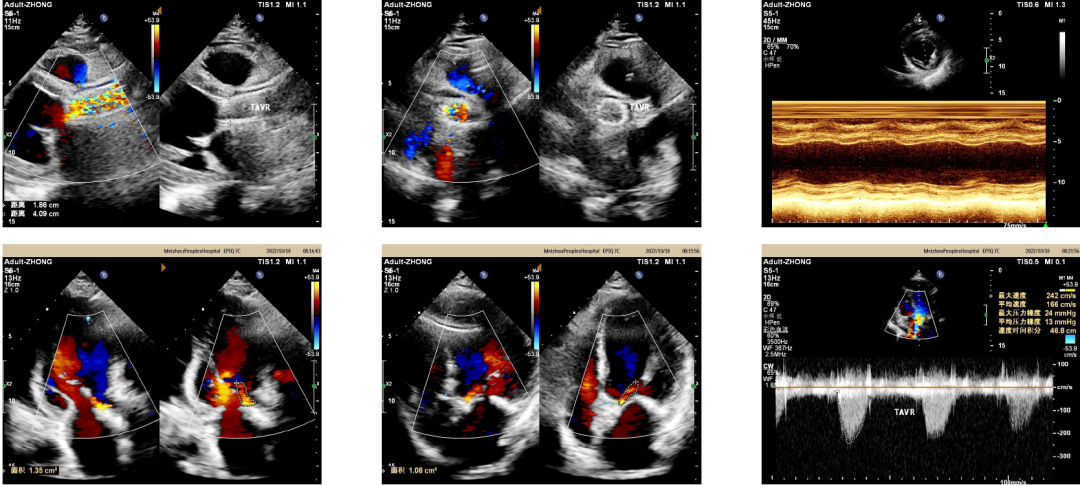

术中超声

出院前超声